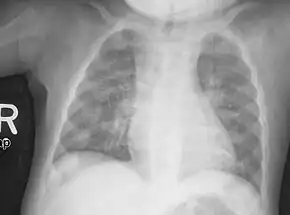

An X-ray or radiograph of an advanced patient with rickets tends to present in a classic way: the bowed legs (outward curve of long bone of the legs) and a deformed chest. Changes in the skull also occur causing a distinctive "square headed" appearance known as "caput quadratum".[18] These deformities persist into adult life if not treated. Long-term consequences include permanent curvatures or disfiguration of the long bones, and a curved back.[19]

- Radiography typically show widening of the zones of provisional calcification of the metaphyses secondary to unmineralized osteoid. Cupping, fraying, and splaying of metaphyses typically appears with growth and continued weight bearing.[47] These changes are seen predominantly at sites of rapid growth, including the proximal humerus, distal radius, distal femur and both the proximal and the distal tibia. Therefore, a skeletal survey for rickets can be accomplished with anteroposterior radiographs of the knees, wrists, and ankles.[47]